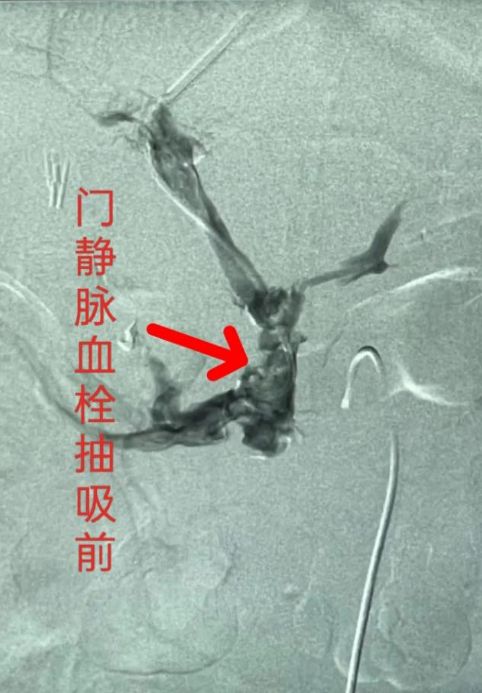

勇担健康使命,铸就时代新功。近日,我院血管介入科成功为一位门静脉血栓形成患者实施了河南省首例经门腔分流通道行门静脉血栓机械抽吸术。

该患者十年前行脾门断流术后门静脉血栓形成、门静脉入肝脏血流受阻,门脉高压形成、继发胃底食道静脉曲张并导致上消化道出血危及生命。门静脉血栓急性期进行有效处理至关重要,因此我们抓住这一关键节点对病人进行紧急手术。术后门静脉回心血流通畅,效果满意。